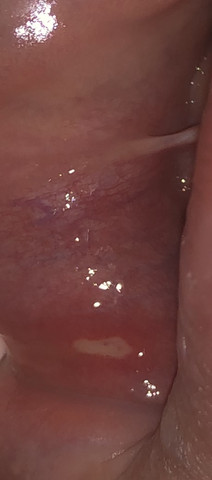

Ein großes, krosses Brötchen oder ein Glas Orangensaft – bei Wunden im Mund verzichtet man auf viele Dinge, die man eigentlich gerne mag Denn wunde Stellen auf der Zunge, am Zahnfleisch oder der Lippeninnenseite brennen und schmerzen z B beim Kauen oder bei Kontakt mit Fruchtsäure. Offene Stellen Die ÖGK sucht Mitarbeiter und Mitarbeiterinnen in ganz Oberösterreich Wir haben 23 Kundenservicestellen, 14 Zahngesundheitszentren, vier Gesundheitszentren für physikalische Medizin und ambulante Rehabilitation sowie drei Gesundheitszentren für Kur und Erholung. Entdecken Sie unsere aktuellen Stellenangebote und werden Sie Teil des Manor Teams Wir freuen uns auf Ihre Bewerbung.

Offene Stellen und kleine Wunden an den Innenseiten der Wangen und Lippen, am Zahnfleisch und an der Zunge können extrem schmerzhaft sein und sich entzünden Aller Anfang ist schmerzhaft In der ersten Phase mit einer neuen Zahnspange müssen sich die verschiedenen Gewebe der Mundhöhle noch an die veränderte Situation anpassen – und das kann ordentlich wehtun. Denn wunde Stellen auf der Zunge, am Zahnfleisch oder der Lippeninnenseite brennen und schmerzen z Zahnprothesenreinigen und möglichst weniger tragen, solange der Mund entzündet ist, 4 Neben Mund, ein Zungenpiercing heilt nach einigen en, sind es auch After/Darm (ja, ja) und Augen. Hallo Community, ich habe letztens einen Pickel im Intimbereich festgestellt und diesen ausgedrückt und mich daraufhin rasiert Am nächsten war die Stelle viel größer und es haben sich rundum auch kleine Pickelchen gebildet und diese eitern alle.

Zudem ist die Mundschleimhaut geschwollen, gerötet oder geschwürig verändert Sie kann brennen, jucken oder bluten Auch ein vermehrter Speichelfluss kann auf eine Mundschleimhautentzündung hinweisen Manchmal sind Stellen der Mundschleimhaut belegt, mitunter kommt es zu Mundgeruch. Senior Immobilienbewirtschafter Eigentümerseiter 100% (m/w) in Zürich;. Eine Lippenentzündung hat verschiedene und vielfältige Ursachen In der Regel wird sie aufgrund von allergischen Reaktionen, viralen sowie auch bakteriellen Infektionen, andauernde Strahlung (z B bei Sonnenbrand), durch ein regelmäßiges Lecken oder aber durch eine so genannte Präkanzerose (Gewebsveränderung mit dem Risiko einer malignen Entartung) einhergehen.